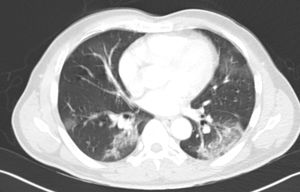

Lab work demonstrated lymphopenia of 11.3% (normal values [NV] 20%–50%) and PCR of 18.6 (NV 0.03–0.05). Chest and abdominal radiographs showed large distention of the colonic loops (Fig. 1) and a slight increase in bibasilar condensation but no infiltrates with compression due to dilated loops of the upper hemithorax. Finally, a computed tomography (CT) scan of the abdomen was requested with expansion to the lung bases (Fig. 2A and B). Emergency CT scan ruled out abdominal disease requiring urgent surgery and revealed notable distension of the dolichosigma with air content; ground glass infiltrates were observed in the left lower pulmonary lobe, which, given the current epidemiological situation, is compatible with COVID infection. Finally, a SARS-CoV-2 PCR was requested, which came back positive.